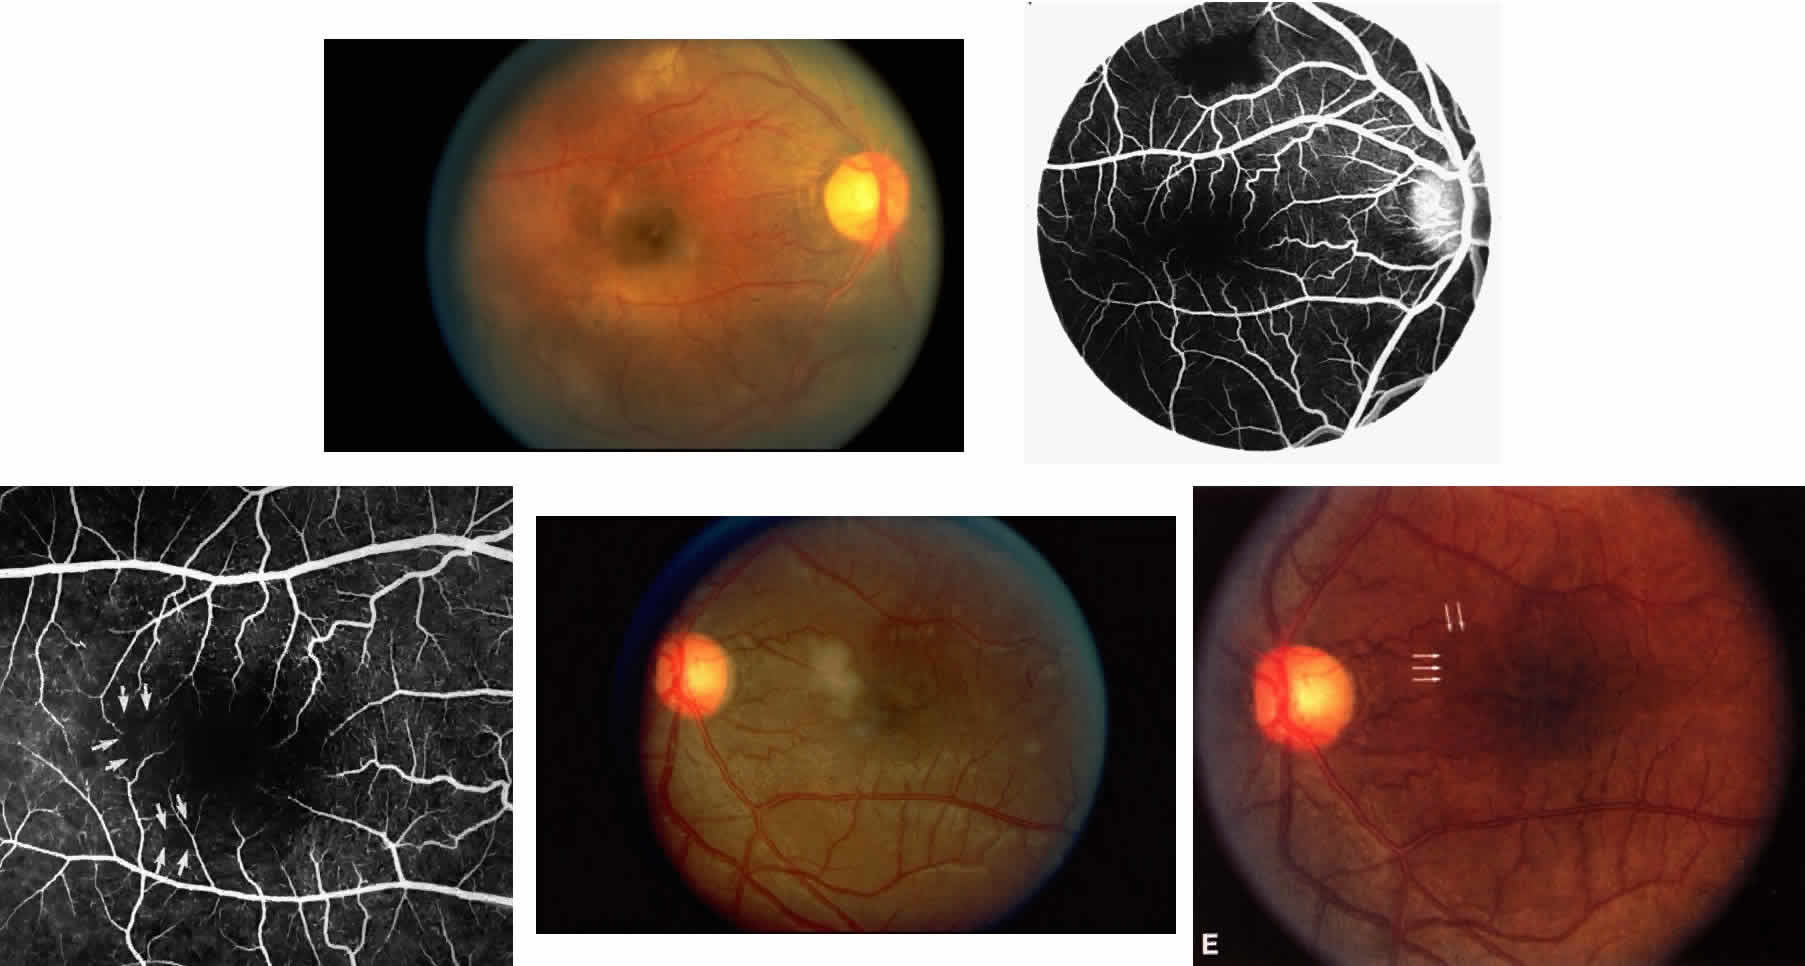

Occlusions of the fine vasculature of the macular and perimacular area have been reported in 10% to 40% of patients with sickle cell disease.18,83,91–99 In the acute phase, the occluded vessel will have a dark red appearance and may appear as a dark line on fluorescein angiography (Fig. 9). Nerve fiber layer infarcts (cotton-wool spots) are seen (see Fig. 8D and E;Fig. 10).100

Other macular and perimacular changes include microaneurysm-like dots, dark and enlarged segments of arterioles, hairpin-shaped venular loops, pathologic avascular zones, and widening and irregularities of the foveal avascular zone (Figs. 11 and 12). In the Jamaican cohort study evaluating children with homozygous sickle cell anemia and SC disease between the ages of 5.0 and 7.5 years of age, no pathologic avascular zones could be identified despite a high incidence of peripheral vascular closure.31 In evaluating patients with homozygous sickle cell anemia, no relationship between ISC counts and macular abnormalities or visual acuity could be found.101 Using fluorescein angiography, investigators have found the foveal avascular zone to be significantly larger in eyes with clinical evidence of sickle cell maculopathy as compared with normal eyes and eyes without clinical evidence of sickle cell maculopathy.102–104

Careful examination by fluorescein angiography, looking for areas of capillary dropout and other capillary abnormalities, is often necessary to identify the macular changes. These changes may be transient, and the macula may appear normal on subsequent fluorescein angiograms (Fig. 13). Although fluorescein angiography may or may not demonstrate reperfusion of a previously occluded capillary bed, a loss of the inner retinal layers results in an ophthalmoscopic focal concavity with an abnormal reflex (retinal depression sign) (see Fig. 8E).105,106 These changes are usually permanent. The retinal depression sign is not pathognomonic of sickle cell disease and may be seen with other arteriolar occlusive diseases, such as embolic retinopathy, vasculitis, and hypertension.

Macular Function Testing in Sickle

Cell MaculopathyThe visual acuity in patients with sickle cell disease is often normal, despite the presence of an enlarged foveal avascular zone or other evidence of sickle cell maculopathy (Fig. 14). In addition, patients with sickle cell maculopathy have a remarkable absence of visual complaints. Although 55% of patients with homozygous sickle cell anemia had abnormal contrast sensitivity, no significant relationship was demonstrated between contrast sensitivity and macular vascular abnormalities.101 Automated visual field analysis has demonstrated significantly larger scotomas in patients with abnormally enlarged foveal avascular zone.102 Color vision testing has revealed a greater incidence of blue-yellow defects in patients with sickle cell retinopathy; however, no significant correlation has been demonstrated between color vision defects and the presence of sickle cell maculopathy.98,107